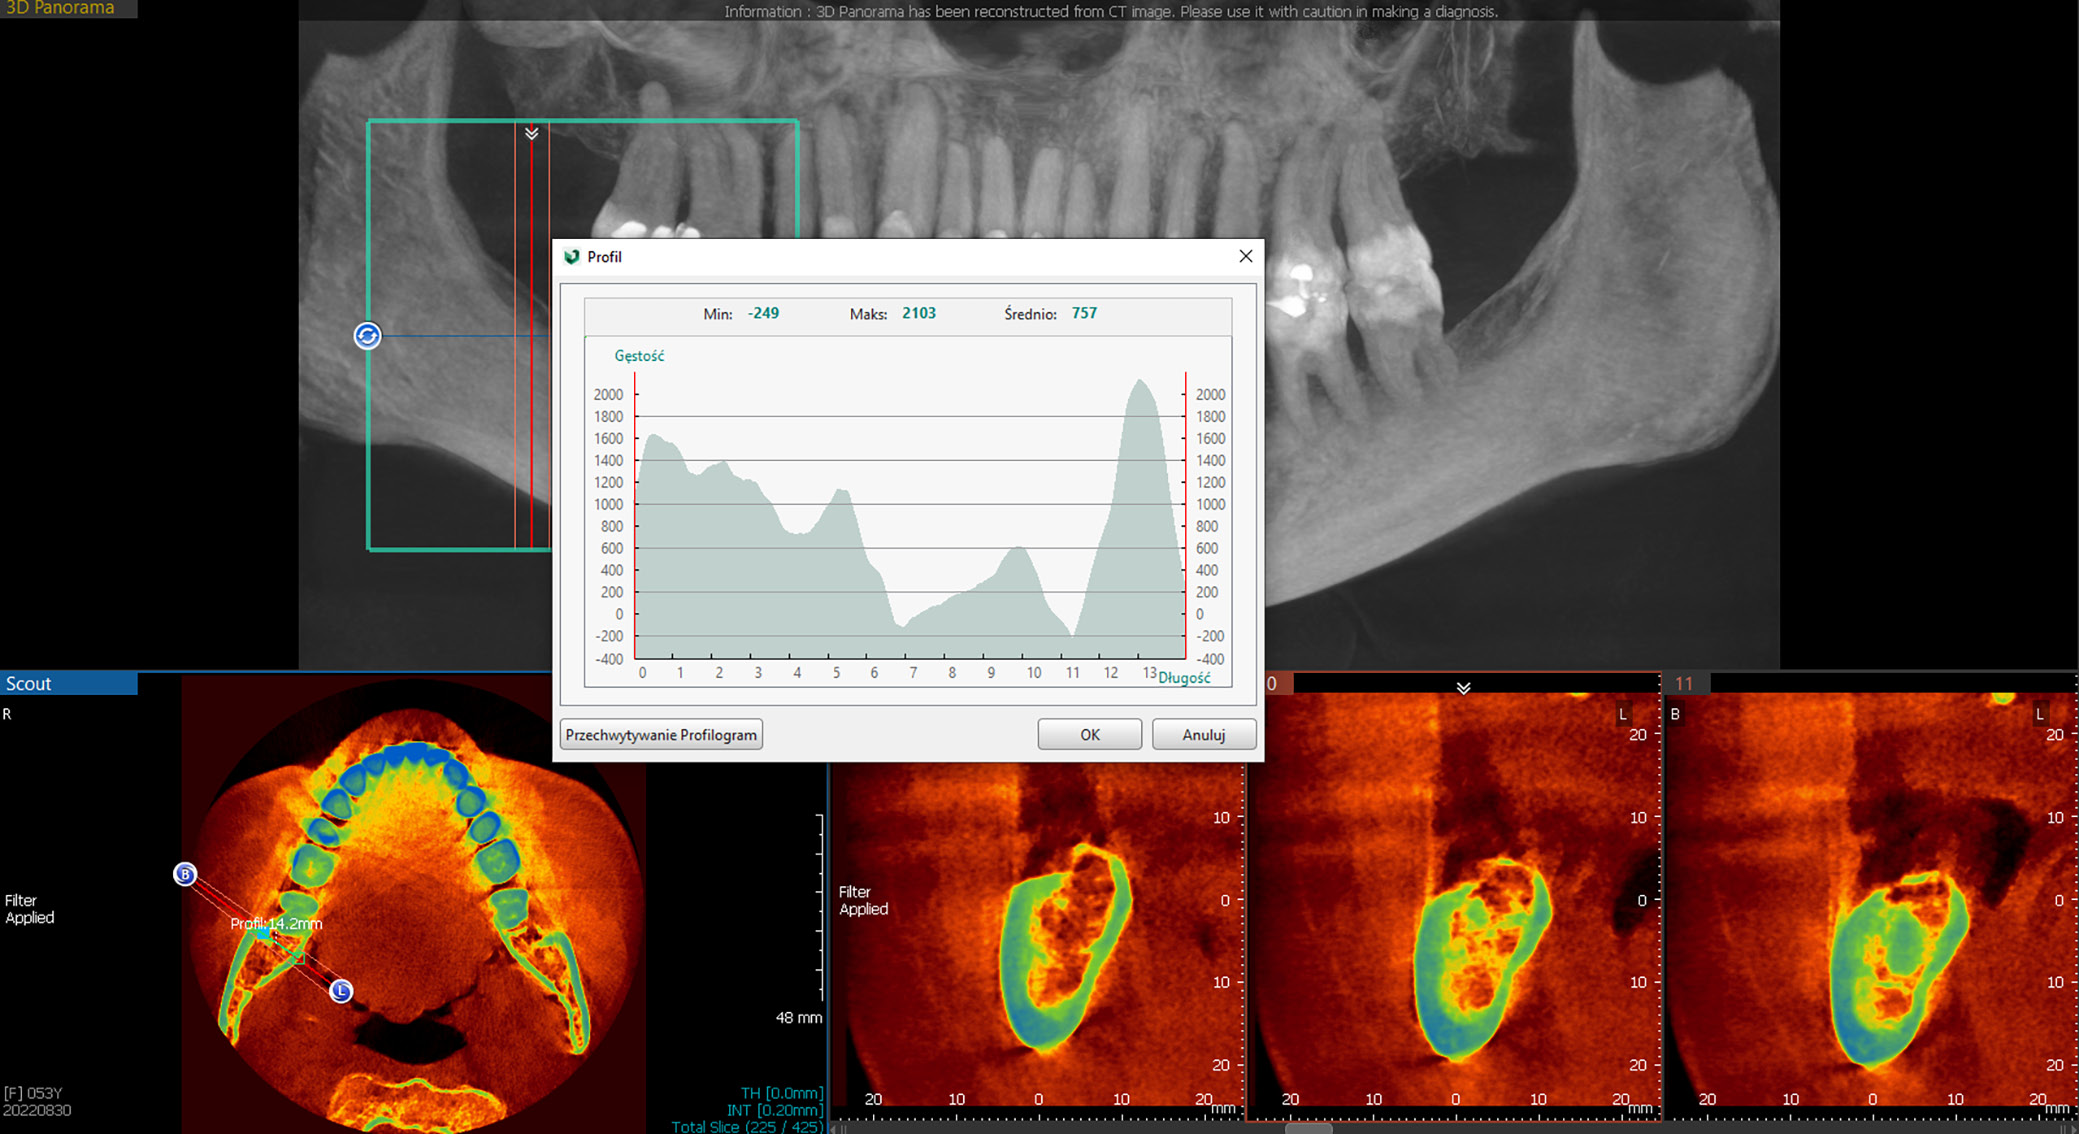

Bone marrow steatosis (BMS)

Measurement of this factor was enabled by the imaging software tools (Figure 7). It was quantified in Hounsfield units (HU), which are based on a calibrated grey-level scale of X-ray images. Originally, HU measurements were used to assess tissue density on CT scans; however, several authors have reported that CBCT images yield similar values.30, 31, 32 Nevertheless, it should be noted that these measurements are approximations that indicate the general direction in which tissue characteristics are changing, and they cannot yet be used with the same precision as CT scans. For example, compact bone typically measures between 662 and 1988 HU, spongy bone between 148 and 661 HU and fat between –205 and –51 HU. Measurements were consistently taken at the end of the retromolar triangle, at the level of the beginning of the ascending ramus of the mandible, using a specialized sub-option of the Vatech software.